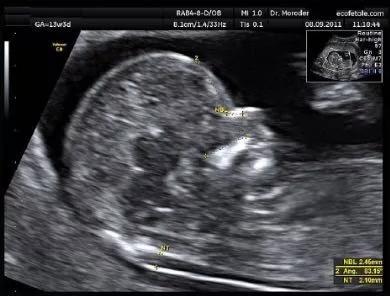

超声上是如下图这样的

我的NT是正常范围的哦!